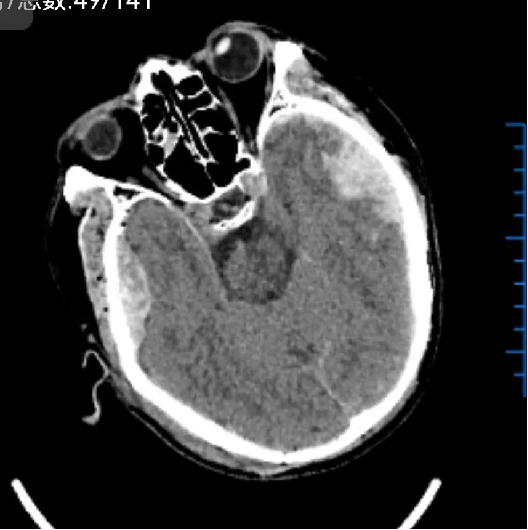

患者汪某,男性,66歲,因重症顱腦(nǎo)損傷,多發肋骨(gǔ)骨折,血氣胸,鎖骨骨折辦理入院緊急手術,醫院神經外科專家團隊為患者行開顱血腫清除+大骨瓣減壓術。手術順利,術後(hòu)恢複滿意。專家團隊將患者手術去除的顱骨骨瓣進行了清洗、滅菌後低(dī)溫冰凍儲存。

術前: